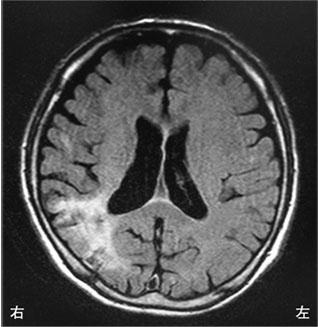

脳梗塞の発生部位によって出現する症状は異なります。この問題では、それぞれの部位における症状を正確に理解することが求められています。

左前頭葉では非流暢性失語が見られるため、この選択肢は誤りです。左半側空間無視は、右頭頂葉後部で見られる症状です。

左放線冠は部位によって様々な症状が現れますが、感覚性失語はWernicke領域で見られるため、この選択肢は誤りです。